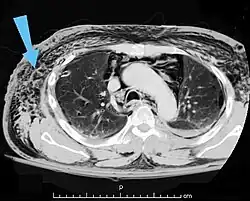

Enfisema torácico em uma tomografia axial como bolhas negras.

O enfisema pode produzir protuberâncias, como nódulos móveis com ruídos crepitantes a palpação. Em uma radiografia de tórax, o enfisema subcutâneo pode ser visto como estriações radioluzentes (escuras) nas áreas com músculos. O ar nos tecidos subcutâneos pode interferir na radiografia do tórax, potencialmente obscurecendo condições graves, como o pneumotórax. Também pode reduzir a eficácia do ultrassom.[8] Também é visível na tomografia e na ressonância magnética como bolhas escuras.